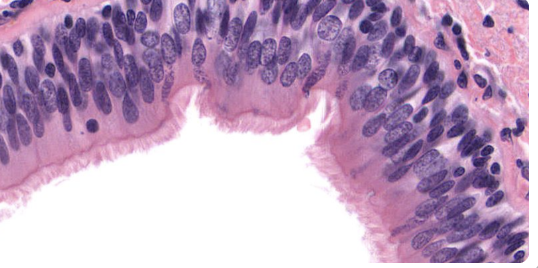

Epithelial Tissues Matching Game

Test your knowledge about epithelial tissues with this fun matching pairs game!